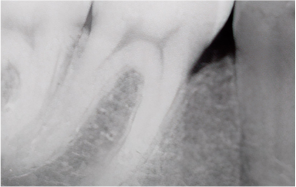

Even when severe periodontal disease has caused gingival recession and alveolar bone resorption, teeth can often be preserved through gum regeneration therapy using Emdogain. This procedure regenerates damaged alveolar bone and surrounding periodontal tissue. By applying Emdogain — a specialized gel that stimulates periodontal tissue regeneration — the supporting structures of the tooth are rebuilt, allowing function and health to be restored without extraction.

Supports regeneration of alveolar bone damaged by chronic periodontitis

Restores periodontal tissue, alveolar bone, and periodontal ligament around teeth

Before & After